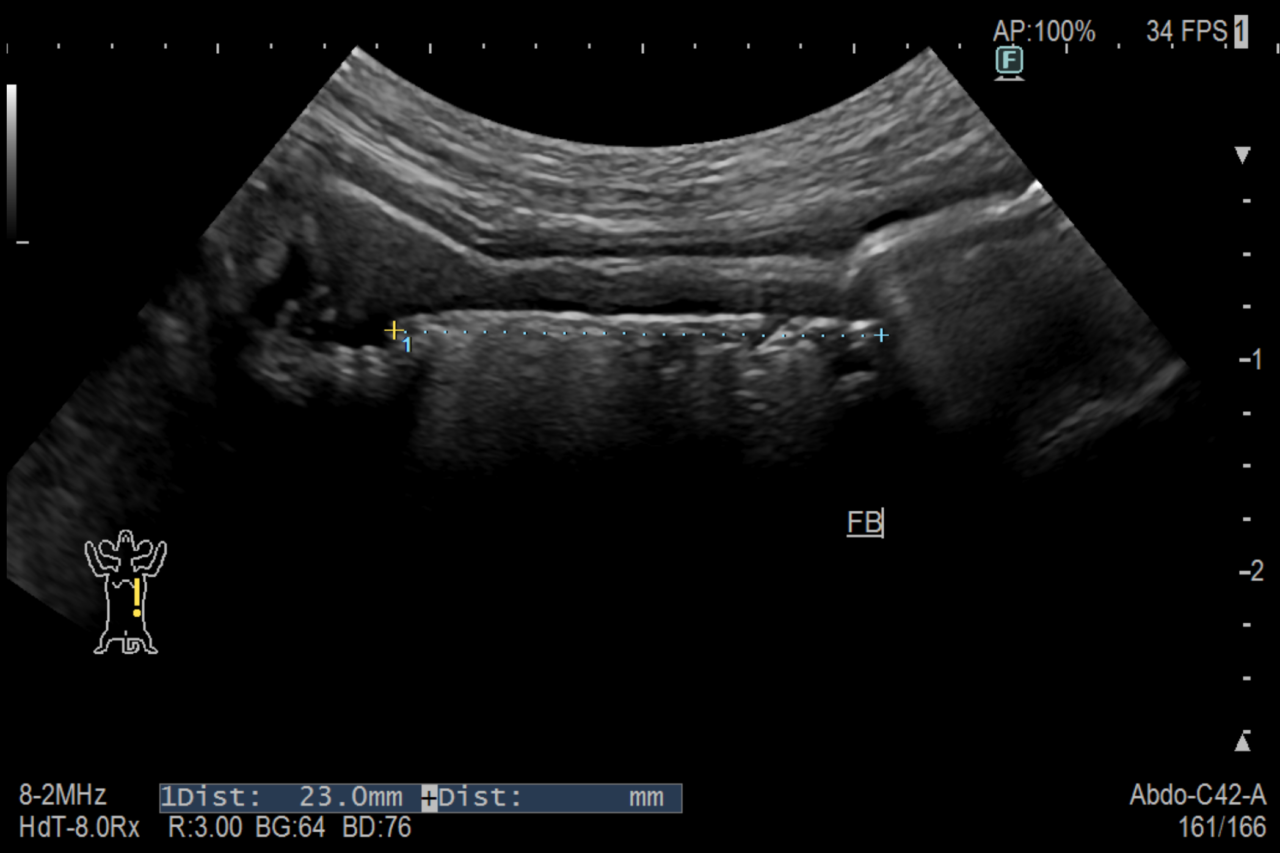

腹部エコーで小腸内に異物を認め、腸閉塞を起こしていると診断してすぐ手術を行いました。